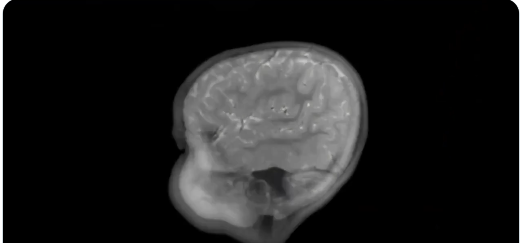

Los investigadores escanearon los cerebros de 60 niños en edad preescolar y lo que descubrieron sobre las pantallas fue realmente asombroso… «El tiempo frente a una pantalla provoca una PÉRDIDA de materia blanca en el cerebro»….

En términos simples, el profesor Mike Nagel lo llama una medida de «DAÑO CEREBRAL»… ¿Qué es la sustancia blanca? Es la parte del cerebro formada por fibras nerviosas aisladas que ayudan a diferentes áreas del cerebro a comunicarse de manera rápida y eficiente.

Actúa como el sistema de cableado del cerebro, transportando señales de una región a otra para que el pensamiento, el movimiento, la emoción y el aprendizaje puedan funcionar sin problemas… «Por lo tanto, si observamos déficits en la producción de mielina en etapas tempranas de la vida, probablemente estemos viendo déficits en la conectividad neuronal»…

«El estudio muestra que cuanto más tiempo pasa un niño expuesto a la pantalla, mayor es la pérdida de materia blanca»… Profesor Mike Nagel.